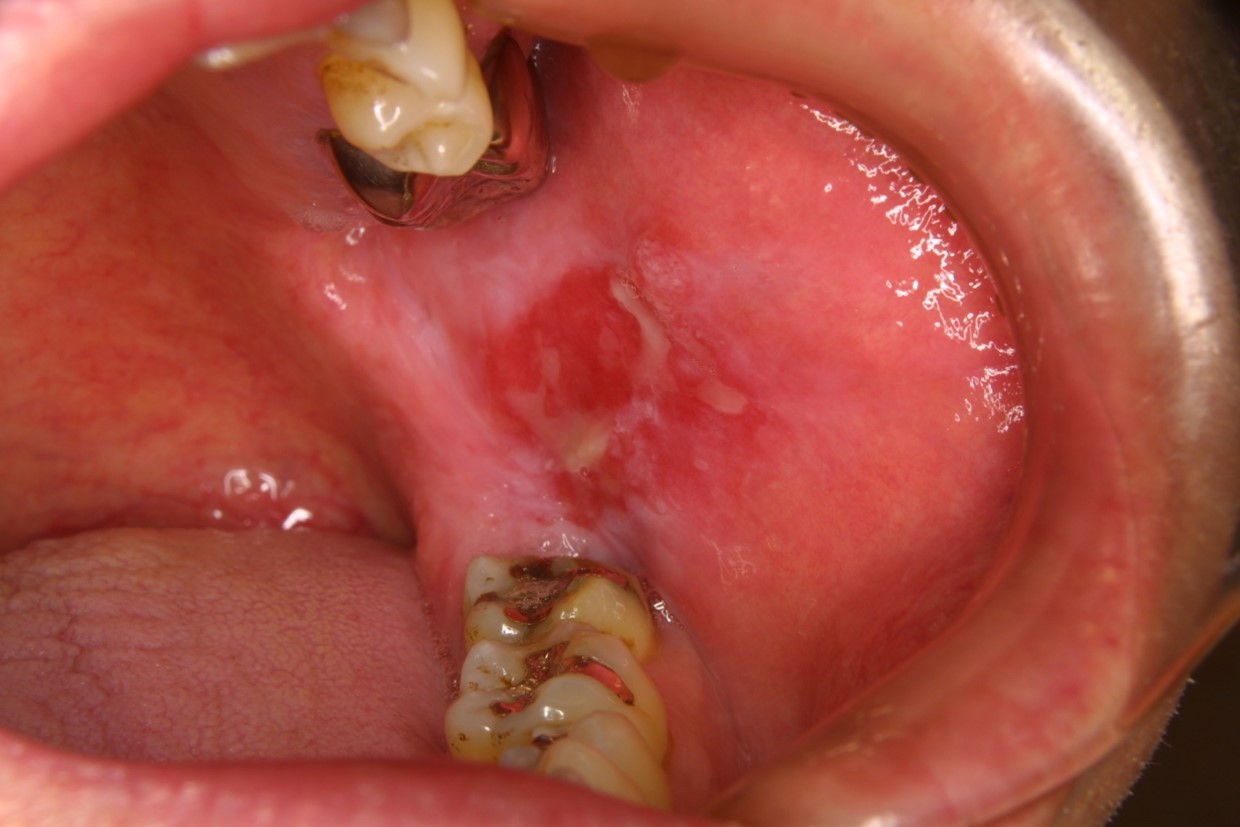

舌、歯肉、頬の粘膜などに白斑(赤い部分が混ざることもある)がある

前がん病変(がんになる前の状態の病変)の中に、白板症というものがあります。この白板症の約6-10%が「がん」になると言われています。